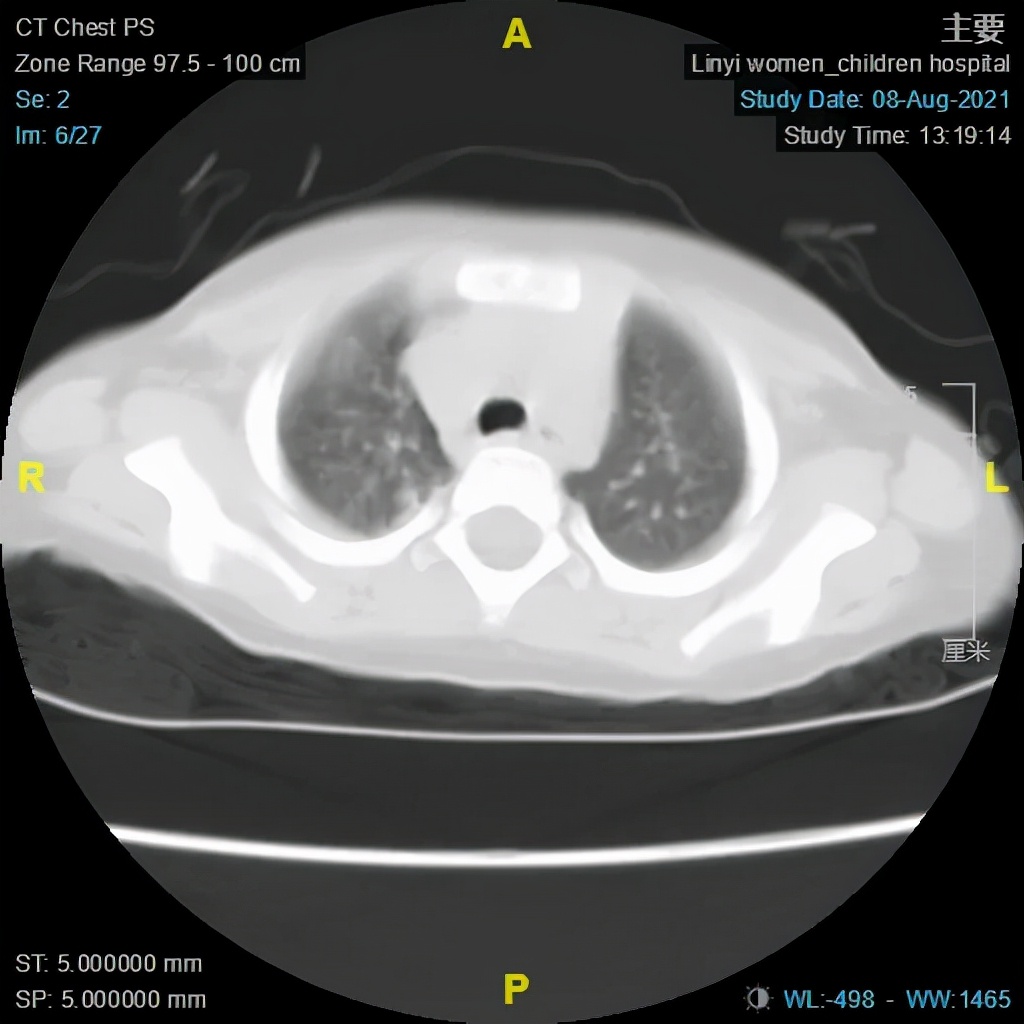

大叶性肺炎术前及术后CT对比图

(电子支气管镜、支气管肺泡灌洗术术后)